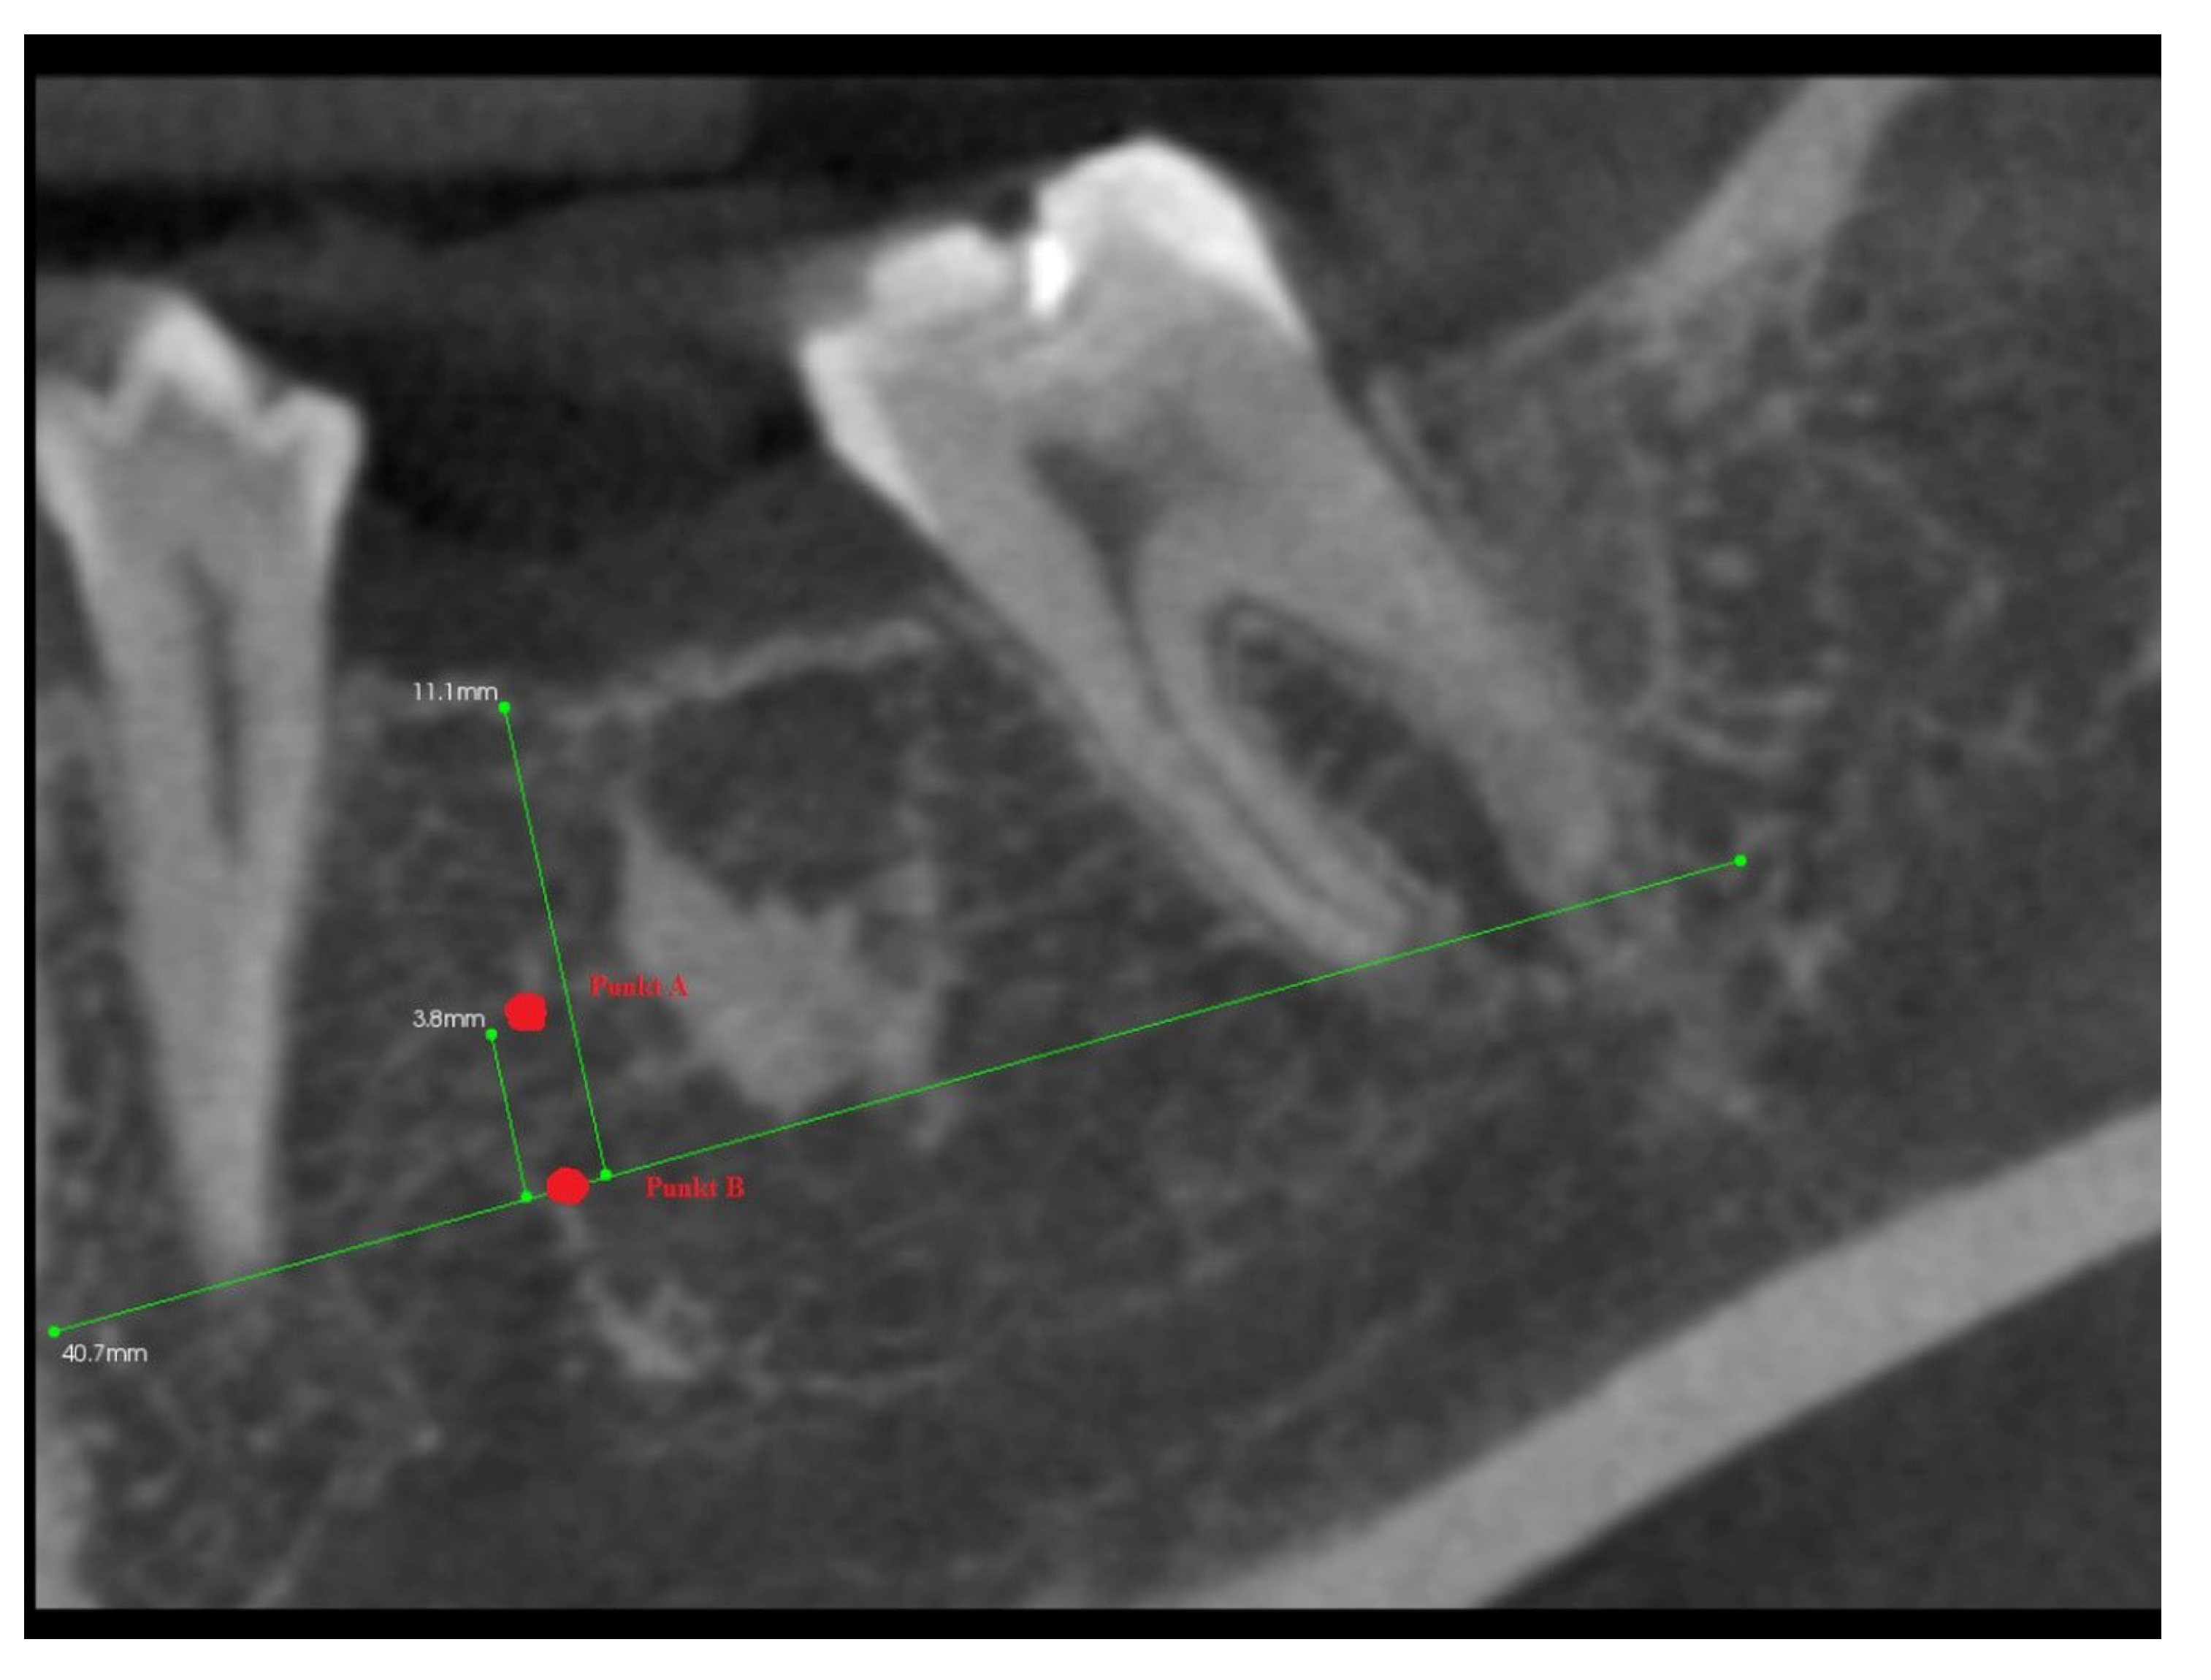

In addition, 6 months after the surgery, another performance of volumetric CBCT limited to the area of the post-extraction alveoli using the Kodak 9000 apparatus was recommended. During these examinations, the alveolar process in the extraction site and grayscale values in the selected measurement points were measured (Figure 6, Figure 7, Figure 8 and Figure 9).

Figure 8.

Grayscale value measurement points.

Figure 9.

Longitudinal imaging of mandibular alveolus in CBCT. Grayscale value measurement 6 months post-extraction.

After 6 months from tooth extraction, grayscale values were assessed. To define the points of measurement, the auxiliary reference lines were defined:

- The A line drawn through the apexes of the teeth adjacent to the post-extraction socket;

- The IC line drawn through the top of the buccal cusps of the teeth adjacent to the pos-extraction socket;

- The midline of the post-extraction socket (alveolus).

Then, the two points of grayscale values were defined (Figure 8):

- Point (A)

- 1/3 of the distance between the A line and the IC line following the midline;

- Point (B)

- At the intersection of the midline and the A line.

3.3. The Results of Mean Values of Grayscale Value Measurements for Two Alveoli (with/without PRF Insertion) after 6 Months

The highly significant differences in the distribution of grayscale values were found in the volumetric tomography in point A (in 1/3 of the section from the side of the alveolar apex) between Group I, that is the alveoli in which platelet-rich fibrin was used, and Group II, that is the control group in which platelet-rich fibrin was not inserted in the alveolus (p = 0.0097). The higher results of this measurement concerned Group I and amounted to 308.16 ± 128.51, whereas in the non-PRF group, they amounted to 279.4 ± 136.23 (Table 4).

Table 4.

Mean values of GVs in CBCT.

The highly significant differences in the distribution of grayscale values were also found in the volumetric tomography in point B (at the intersection of the midline of the alveolus and the line drawn through the adjacent teeth apexes) and, again, the higher results of this measurement concerned Group I, that is the alveoli where platelet-rich fibrin was used, and amounted to 333.1 ± 131.22, whereas in the non-PRF group, it was 305.54 ± 139.12 (Table 4).